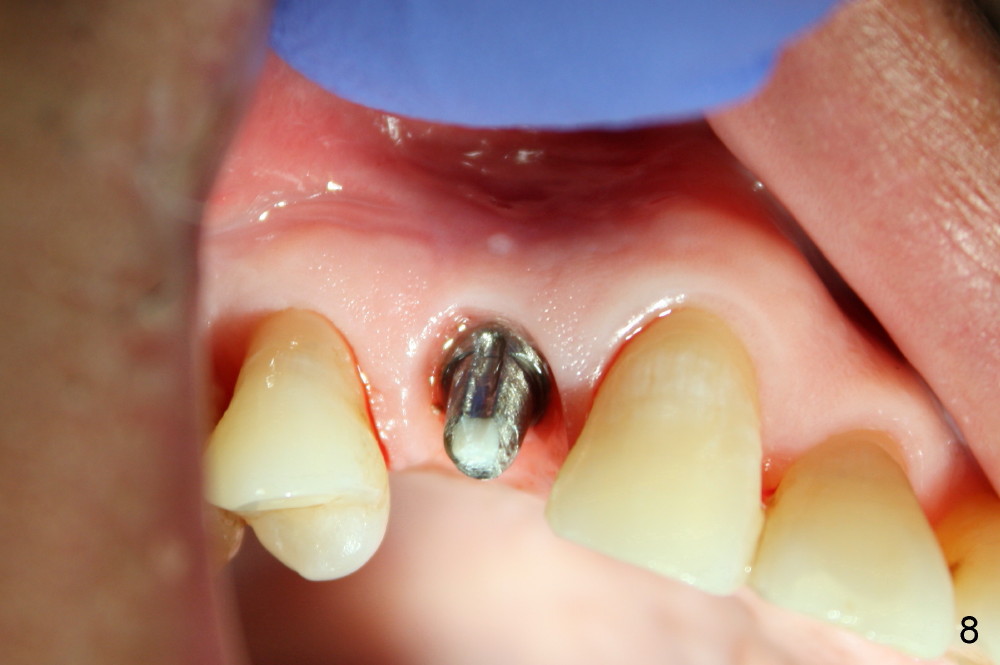

A provisional is fabricated immediately after extraction and implant and definitive abutment placement (Fig.3,4: P). The provisional hold the papilla in place (Fig.3 *). There is no occlusal contact with the opposing dentition (Fig.4 ^). The gingiva looks purplish due to difficult extraction. The tooth keeps fracturing while being extraction. The bone is dense. On the other hand, the dense bone helps achieve primary stability of the implant.

The patient returns 6 months postop for impression of a permanent restoration. The gingiva with knife-edged papillae adapts to the provisional (Fig.7). The gingiva looks healthy when the provisional is removed (Fig.8). The buccal bone resorption seems to be minimal, as compared to Fig.1,2. There is no bone loss between immediately postop (Fig.9 I; implant), 4.5 months postop (Fig.10 A: abutment), 4 and 7 months post cementation (Fig.11,12 C: crown). Soft and hard tissue morphology remains normal 7 months post cementation (Fig.13). No bone loss is observed 15 months post cementation (Fig.14). The papillae (Fig.15) and bone (Fig.16,17) remain stable 29 months post cementation.